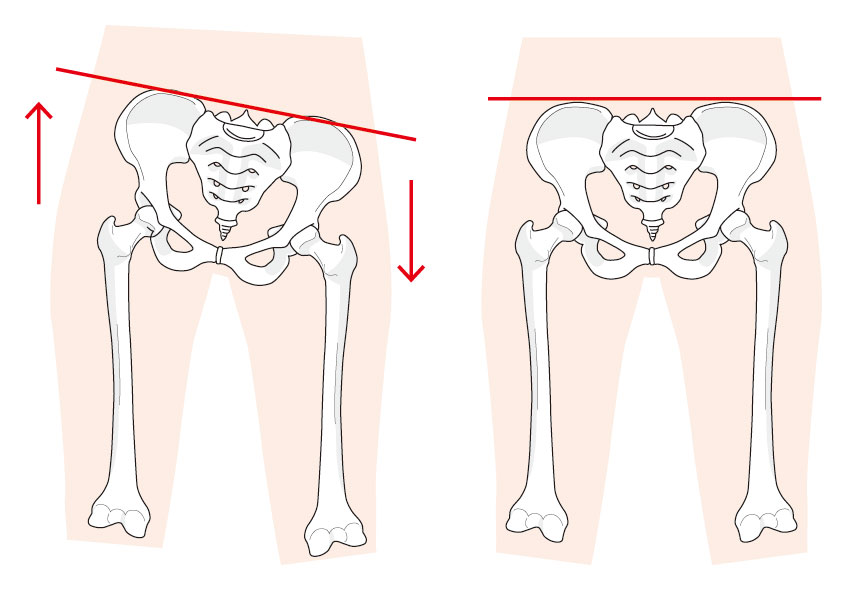

骨盤矯正- 骨盤矯正

スタイルを整え隠れた症状も改善する貴女の為の骨盤矯正